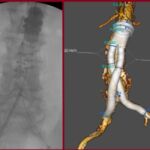

Ανεύρυσμα κοιλιακής αορτής: Mε stent-graft

Η ενδαγγειακή αποκατάσταση ανευρύσματος κοιλιακής αορτής με stent-graft είναι ελάχιστα επεμβατική μέθοδος κατά την οποία τοποθετείται ειδικό ενδομόσχευμα στην αορτή για την απομόνωση του ανευρύσματος.